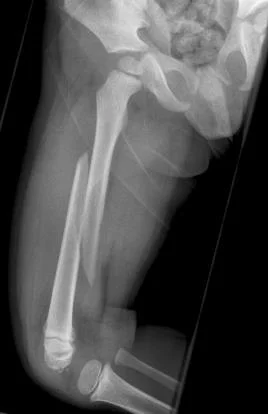

Pathological Fractures

- Fractures caused by trivial force on abnormally weak bone. Seen in:

- Local bone disease

- Osteomyelitis

- Benign tumors and Bone cysts

- Malignant tumors and metastasis

- Generalized disease

- Metabolic: osteoporosis, rickets

- Congenital: osteogenesis imperfecta

- Others: Paget’s disease